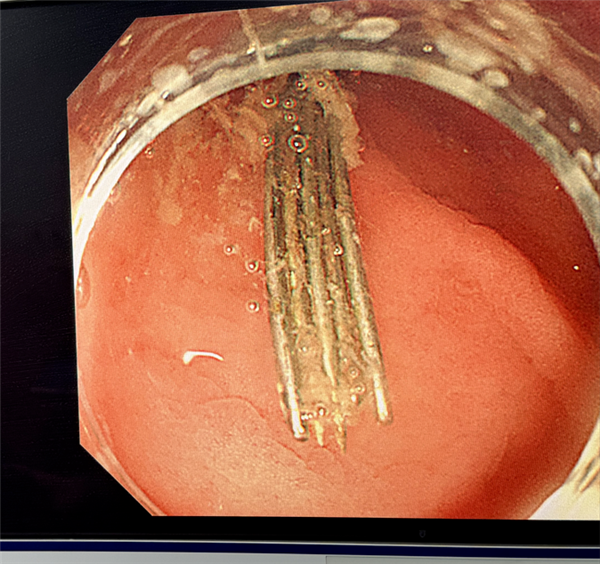

内镜缓缓进入胃腔,屏幕上的画面让人不寒而栗:多根绣花针散落在胃内,绣花针细小、光滑、数量多,且部分紧贴胃壁,操作稍有不慎,就可能造成二次损伤,手术难度极大。

好在医生凭借丰富的临床经验和精湛操作,经过三个小时的连续奋战,最终12根长4–5厘米的绣花针被完整、安全地全部取出。